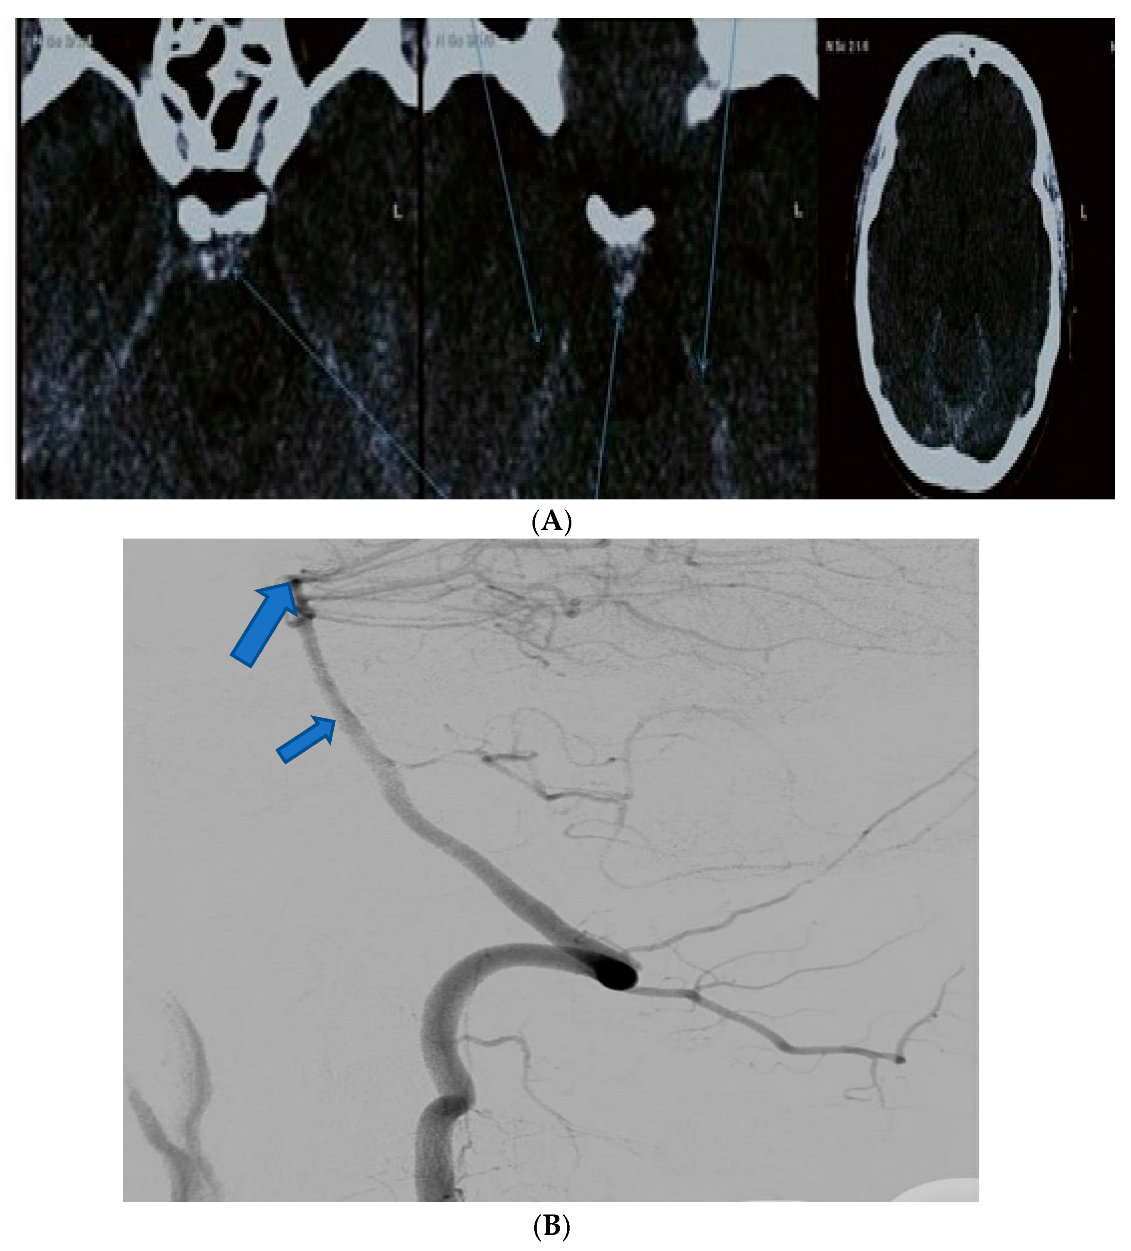

| 54 | F | Diplopia, headache | Native CT scan, CTA | I | I | Mild vasospasm, mild hydrocephaly | 2 | Nimodipine |

| 61 1 | M | Flaccid tetraplegia, altered Mental status | Native CT scan, DSA | IV | IV | Severe vasospasm, hydrocephalus | 6 (deceased) | Nimodipine, mannitol |

| 37 | M | Headache, diplopia | Native CT scan, DSA angiography | II | II | None | 3 | Nimodipine |

| 48 | F | 3rd nerve palsy, pupillary anomalies | Native CT scan, CTA | II | II | Mild vasospasm | 2 | Nimodipine |

| 41 2 | M | Headache, diplopia | Native CT scan, DSA | III | III | Mild vasospasm | 3 | Nimodipine, mannitol |

| 59 | M | 3rd nerve paresis, pupillary anomalies, hemiplegia | Native CT scan, DSA angiography | V | IV | Hydrocephalus, moderate vasospasm | 4 | Nimodipine, mannitol |

| 44 | F | Right internuclear ophthalmoplegia | Native CT scan, CTA | III | I | None | 1 | Nimodipine |